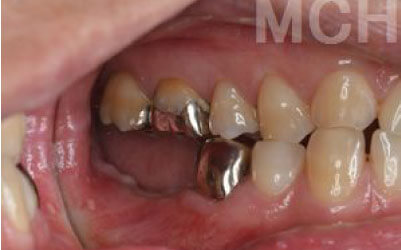

私たちが噛むとき、歯には何十キロもの力がかかっています。そのため、歯の本数が減るほど、残った歯にかかる負担は大きくなります。ブリッジ治療の場合も、失った歯にかかっていた力を前後の健康な歯が支えることになります。その結果、残っている歯には、抜歯前よりも1.5倍から2倍ほど強い力がかかるのです。

ブリッジなどの治療では、支えとなる前後の歯を大きく削らなければなりません。場合によっては、虫歯でなくても歯の神経を抜くことがあり、神経を抜いて被せ物をすると、その歯は急速に寿命が短くなってしまいます。一方でインプラント治療は、前後の歯を削ったり神経を取ったりする必要がありません。健康な歯をできるだけ残すことは、歯の寿命を延ばすために非常に重要です。

最も大きな違いは、前後の歯の寿命が変わることです。

ブリッジは、抜けた部分の前後の歯を大きな虫歯と同じくらい削る必要があります。

さらに、抜けた歯の力を前後の歯が負担するため、ブリッジを支える歯には常に1.5倍の力がかかります。

1)ブリッジ

2)歯を大きく削る+支えの歯に1.5倍の力がかかる

3)前後の歯の寿命が著しく減る

ブリッジの支えの歯は、データでは10年以内に68%が抜歯になります。